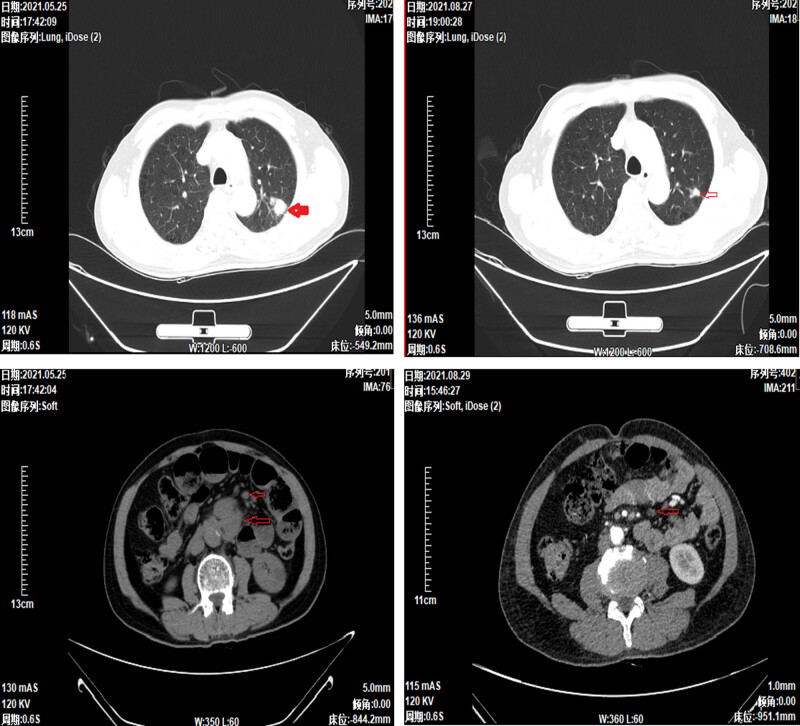

Patients with small cell lung cancer (SCLC) typically exhibit a poor prognosis, often receiving diagnoses at an advanced stage. Despite recent advances in immunotherapy, the median survival remains approximately one year. Gastrointestinal metastases from lung cancer, based on clinical experience, are exceedingly rare and associated with dire prognoses. This article details the diagnosis and management of an unusual case of SCLC with gastrointestinal metastasis. The patient's survival was notably prolonged compared to typical SCLC outcomes, providing significant clinical insight.